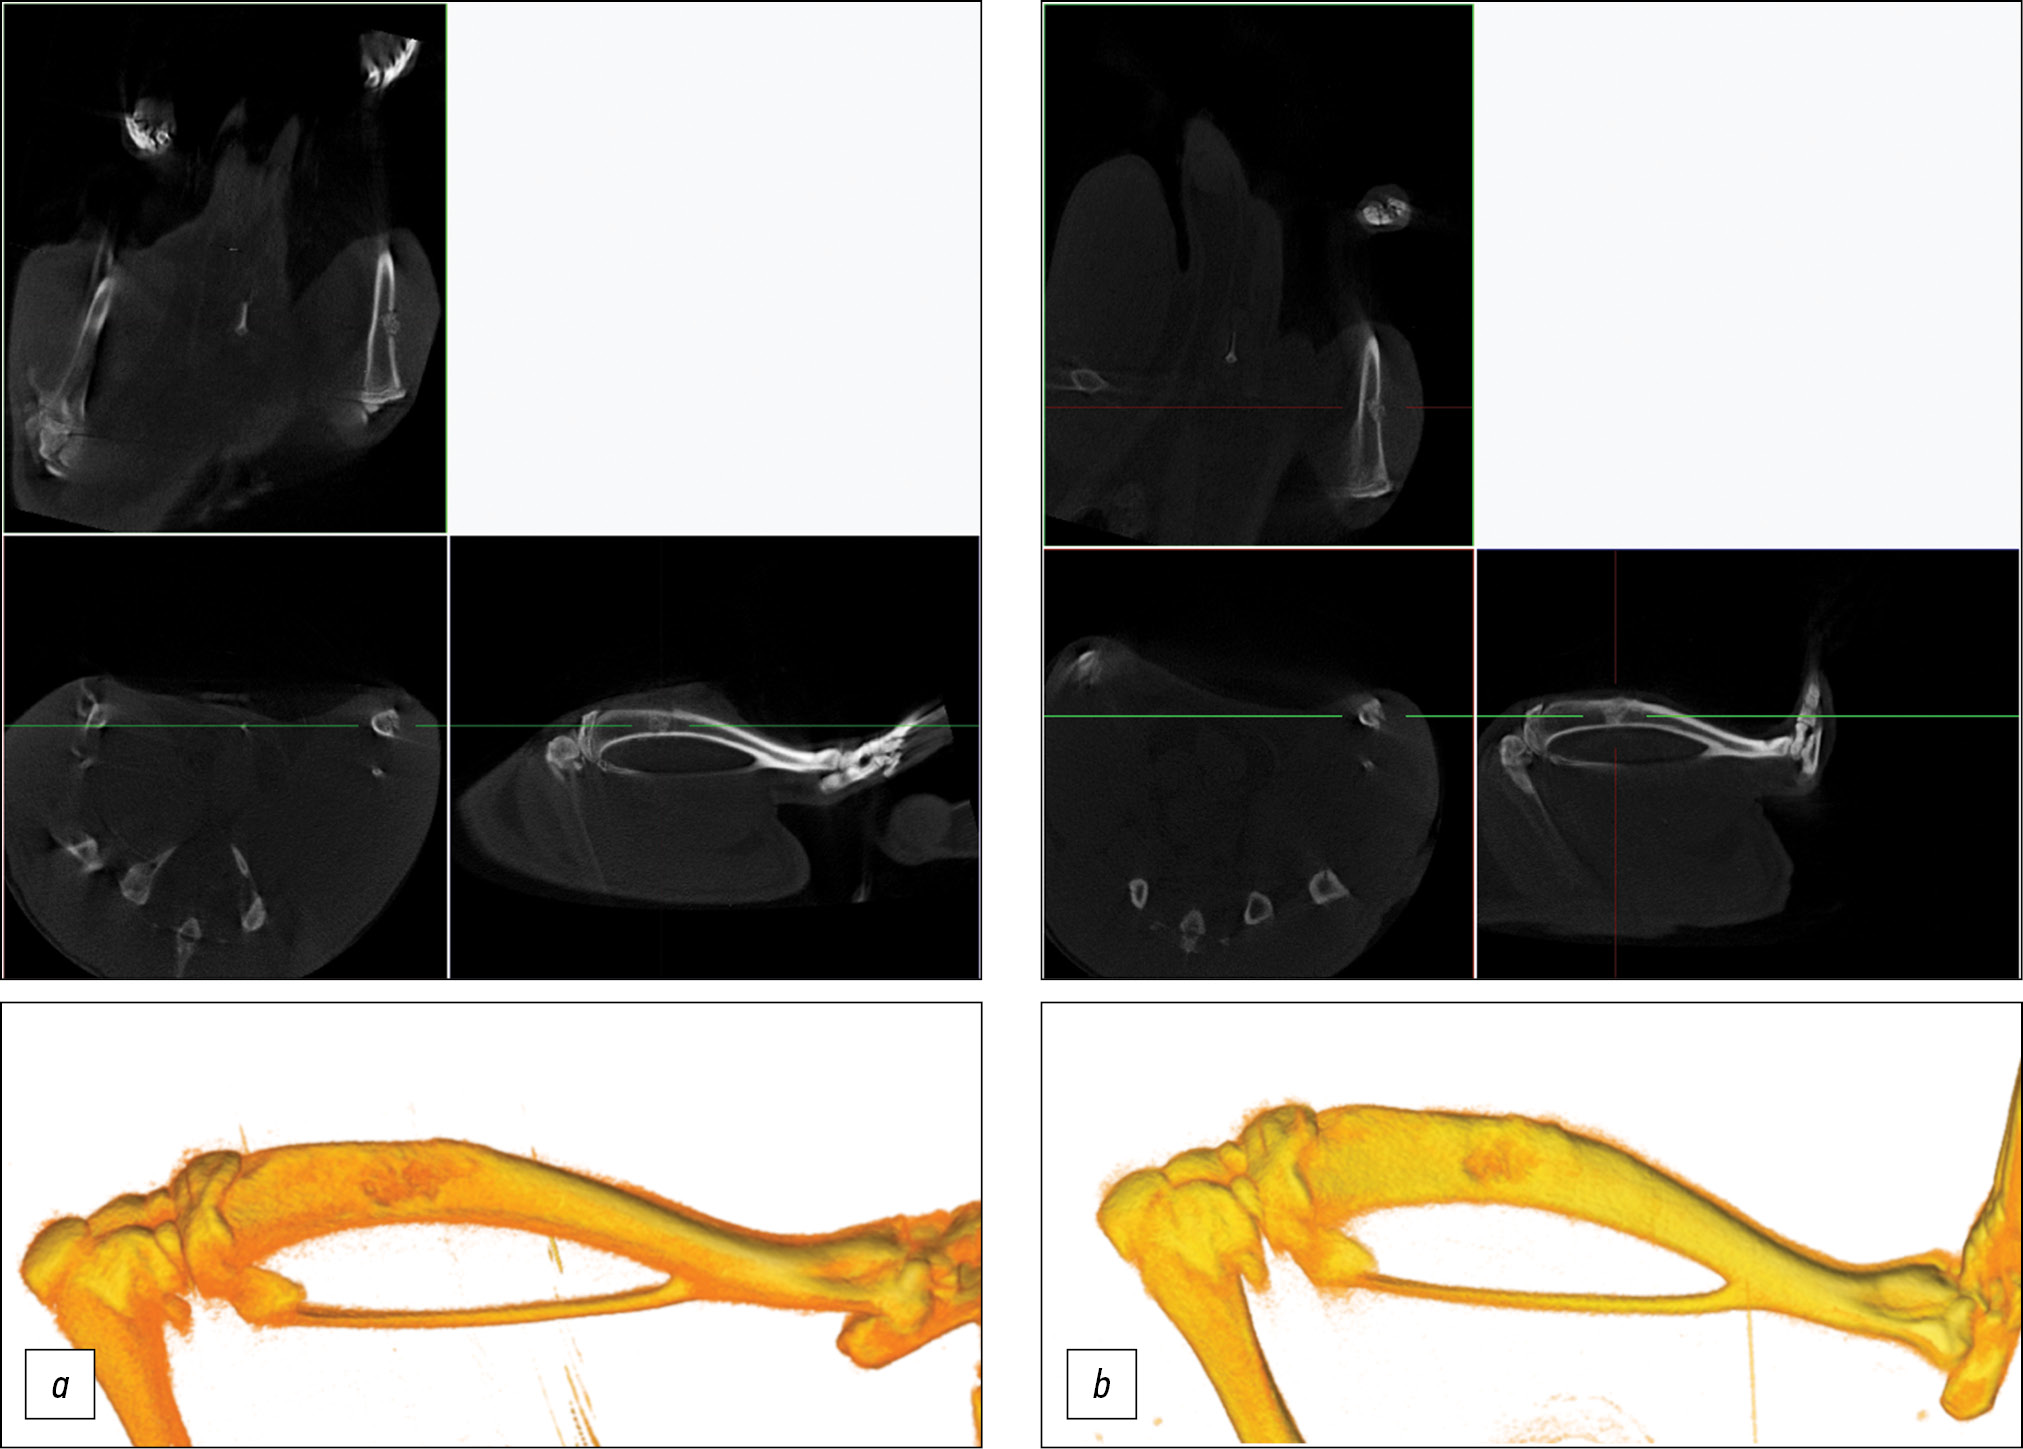

A micro-CT was conducted in vivo after surgery and postmortem at 2 weeks and 1 month after implantation. Micro-CT was performed using a Bruker SkyScan 1178 scanner (Kontich, Belgium) with a voltage of 65 kV and a current of 615 μA, and a 0.5 mm A1 filter was used. The spatial resolution was 84 μm/pixel. The sections were reconstructed using NRecon software, version 1.6.10.4, and 3D reconstructions were performed using CT Vol 2.2.0.0 program.

Based on CT data, the model of bone perforation in in vivo experiments showed that after implantation, the material adhered tightly to the bone walls and was located in the bone defect area, without any migration (Fig. 5). After 14 days, the material remained visible in the projection of the defect; however, partial resorption was observed. The area of the defect decreased, and regeneration formation from the bone edges was observed. No radiologic signs of inflammation were found. After 30 days of implantation, the material was observed in the projection of the defect, and significant resorption of the material was determined. It was mainly preserved in the medullary canal (Fig. 6). The defect area significantly reduced, and a pronounced bone callus with formed bone bridges running along the surface of the implanted material was noted.

Fig. 6. Orthogonal projections and 3D model of the rat tibia: a — at the time of implantation, b — after 30 days.

By day 30 after implantation, the implant gradually resorbed, and relatively mature bone structures with a lamellar structure and osteons formed in the bone defect area. Furthermore, a cellular array of hematopoietic bone marrow was determined. At this point, the defect was almost closed because of the intermedial bone callus, and the implanted material was found in separate small fragments without osteocytes (Fig. 8b), and no signs of inflammatory reactions were found in any of the cases studied. No pronounced leukocytic or histiocytic reaction and no formation of giant multinucleated foreign body cells were detected.